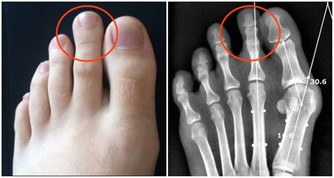

右臉頰長痘可能是肺的問題

右臉頰痘痘是肺部有炎症的反映。如果你肺火上升、喉嚨乾燥、痰多咳嗽,留意一下右臉頰痘痘。

建議:禁食易敏食物。停止吃海鮮和芒果、酒類食物等易敏食物,過敏會讓你的氣管、支氣管、肺部更加不適。